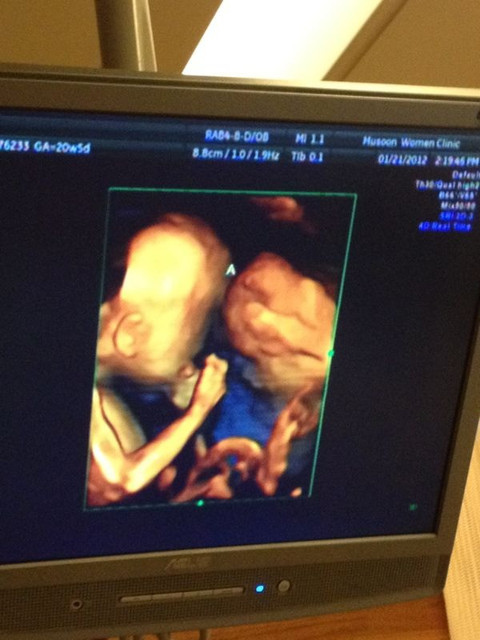

接著,醫生讓我們看看兩個小寶貝♥

哈哈哈哈~動來動去,一直在吃小手手和揉眼睛真的是可愛極了啦!